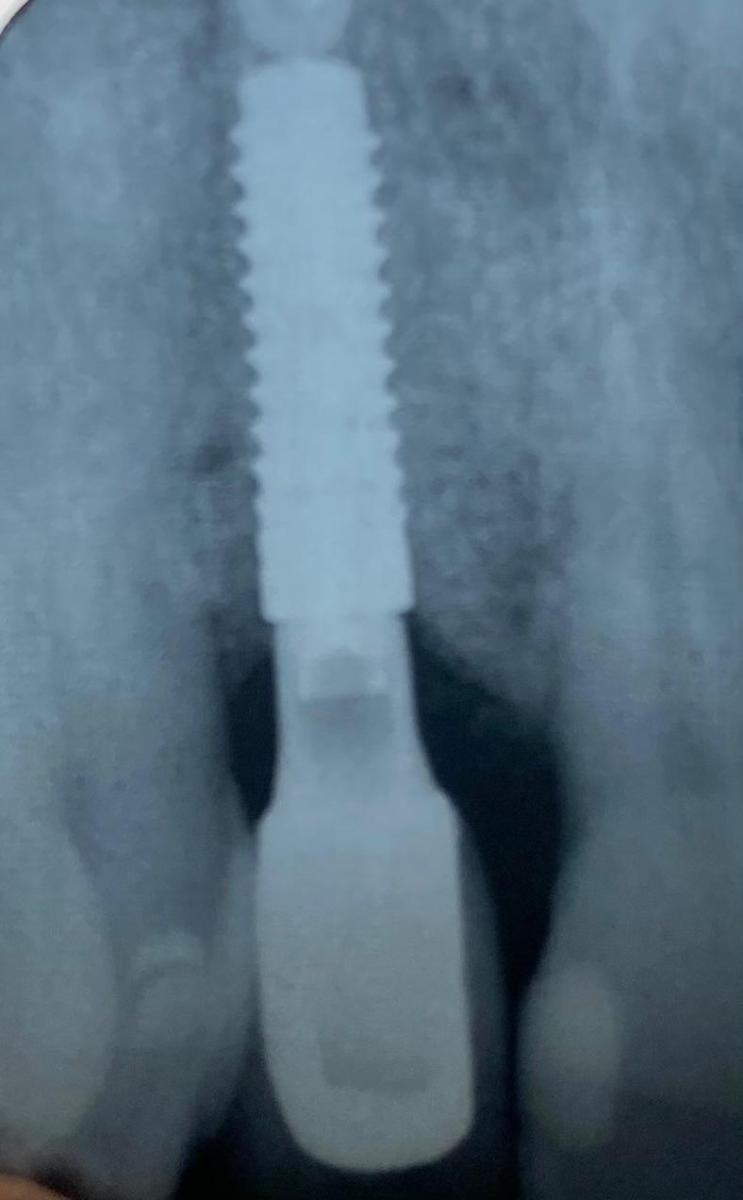

Single implant case in the anterior region, following digital planning to ensure precise positioning and optimal aesthetic outcome. Pre-operative CBCT analysis was used to assess bone volume and guide implant angulation, allowing for a prosthetically driven approach.

The implant was placed with careful attention to surrounding anatomical structures and soft tissue preservation. This allowed for stable integration and proper support of the final restoration. Healing was uneventful, with good tissue response and maintenance of gingival architecture.

The final crown was designed to match the adjacent teeth in shape, colour, and emergence profile, achieving a natural and harmonious result. Functional stability and aesthetic integration were both prioritised, delivering a predictable long-term outcome.